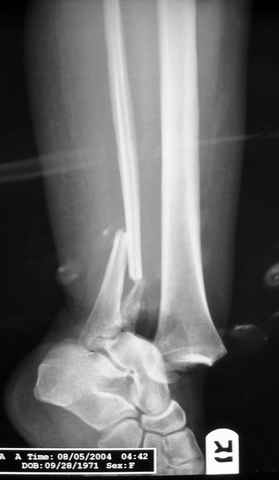

Еще, кстати, о фиксации лодыжки, если уж непременно хочется ее отдельно стабилизировать - при таком характере перелома замечательно должен сработать предложенный проф. Лазаревым с соратниками способ фиксации напряженной V-образной спицей. Опять же, открытая репозиция не нужна, мы делаем непрямую репозицию именно аппаратом. В приложении пример, там перелом малоберцовой куда менее поперечный, чем в данном случае, но все равно получилось закрыто без пластинки.

A propos fibular fixation if one is eager to stabilize it separately. In the fracture pattern a way of closed fixation by V-shaped stressed wire (advanced by colleagues from Moscow, prof. Lazarev A.F. et al.) must be excellent. We use indirect closed reduction by the external fixator. Example attached, that fibular fracture is even more suitable for plating but the wire did the job.